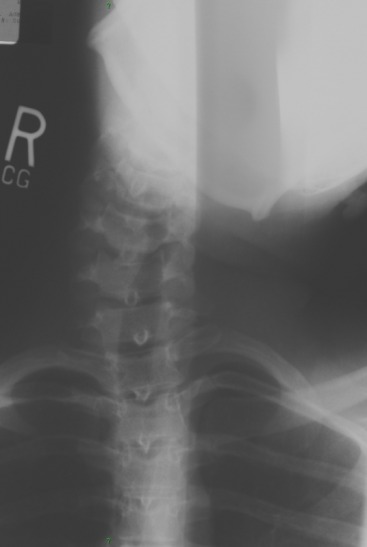

17 year old male post MVA.

1. Describe your findings.

2. What are some of the causes this condition?